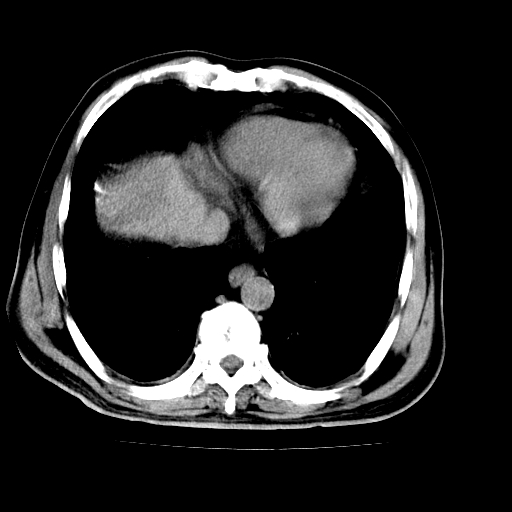

男,66岁,上腹部不适、黄染一周。彩超示:肝左叶占位,肝内胆管扩张,胆总管扩张,胆总管占位?

肝左叶不规则软组织肿块影,边缘不规整邻近肝实质受累分界不清;肝内胆管(左叶)明显扩张成“软藤状”,诊断:肝左叶胆管细胞癌。

肝左叶占位性病变,并胆管扩张,符合胆管细胞癌ct表现,门脉左支受累,左肾囊肿。窗宽太窄了,其他的看不清

左叶胆管细胞癌累及胆总管,门脉左支受侵,慢性胆囊炎胆结石,左肾小囊肿